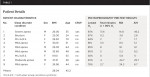

An informed consent form was signed by all participants in the study. The nine OSA patient volunteers (4 male, 5 female) from a sleep apnea clinic included eight who either refused PAP therapy or were found noncompliant after attempting PAP therapy and one who was currently compliant with PAP therapy. Patients were included if they were 18 or older, with OSA diagnoses, not pregnant, and willing to try OAT. Patient demographic data and pretest measures were collected (Table 1). OSA was diagnosed based upon a preliminary overnight polysomnography (PSG) study. The PSG studies were performed using American Academy of Sleep Medicine standards, and results were interpreted by a board-certified sleep physician.

Table 2 summarizes the results of each patient’s adjusted mandibular position along with the pre- and post-test airway volume. Figure 2 and Figure 3 show pre- and post-test CBCT scans of patient No. 5, and Figure 4 shows each patient’s A-P and vertical setting with resulting area airway opening and volumetric increases.

Pre- and post-test results indicate at least three conclusions. First, each person’s mandibular adjustment needs are unique and require an individual approach to adjusting their mandible for oropharynx patency. As shown in Table 2, A-P final measurements varied from -3.5 mm to +4 mm and vertical measurements varied from 6 mm to 8.5 mm. The adjustment to the A-P does not appear to covary with adjustment to the vertical (r = -0.20, n.s.). As shown in Table 2, some airways opened with the most adjustment to A-P, some required most adjustment to vertical, and some required both. The absence of a correlation between adjustment size and change in cross-sectional airway was also found by Gale et al.13 If confirmed with a larger sample size, this indicates that personal adjustment for airway openings needs to be accomplished without any a priori set of adjustments as the goal.